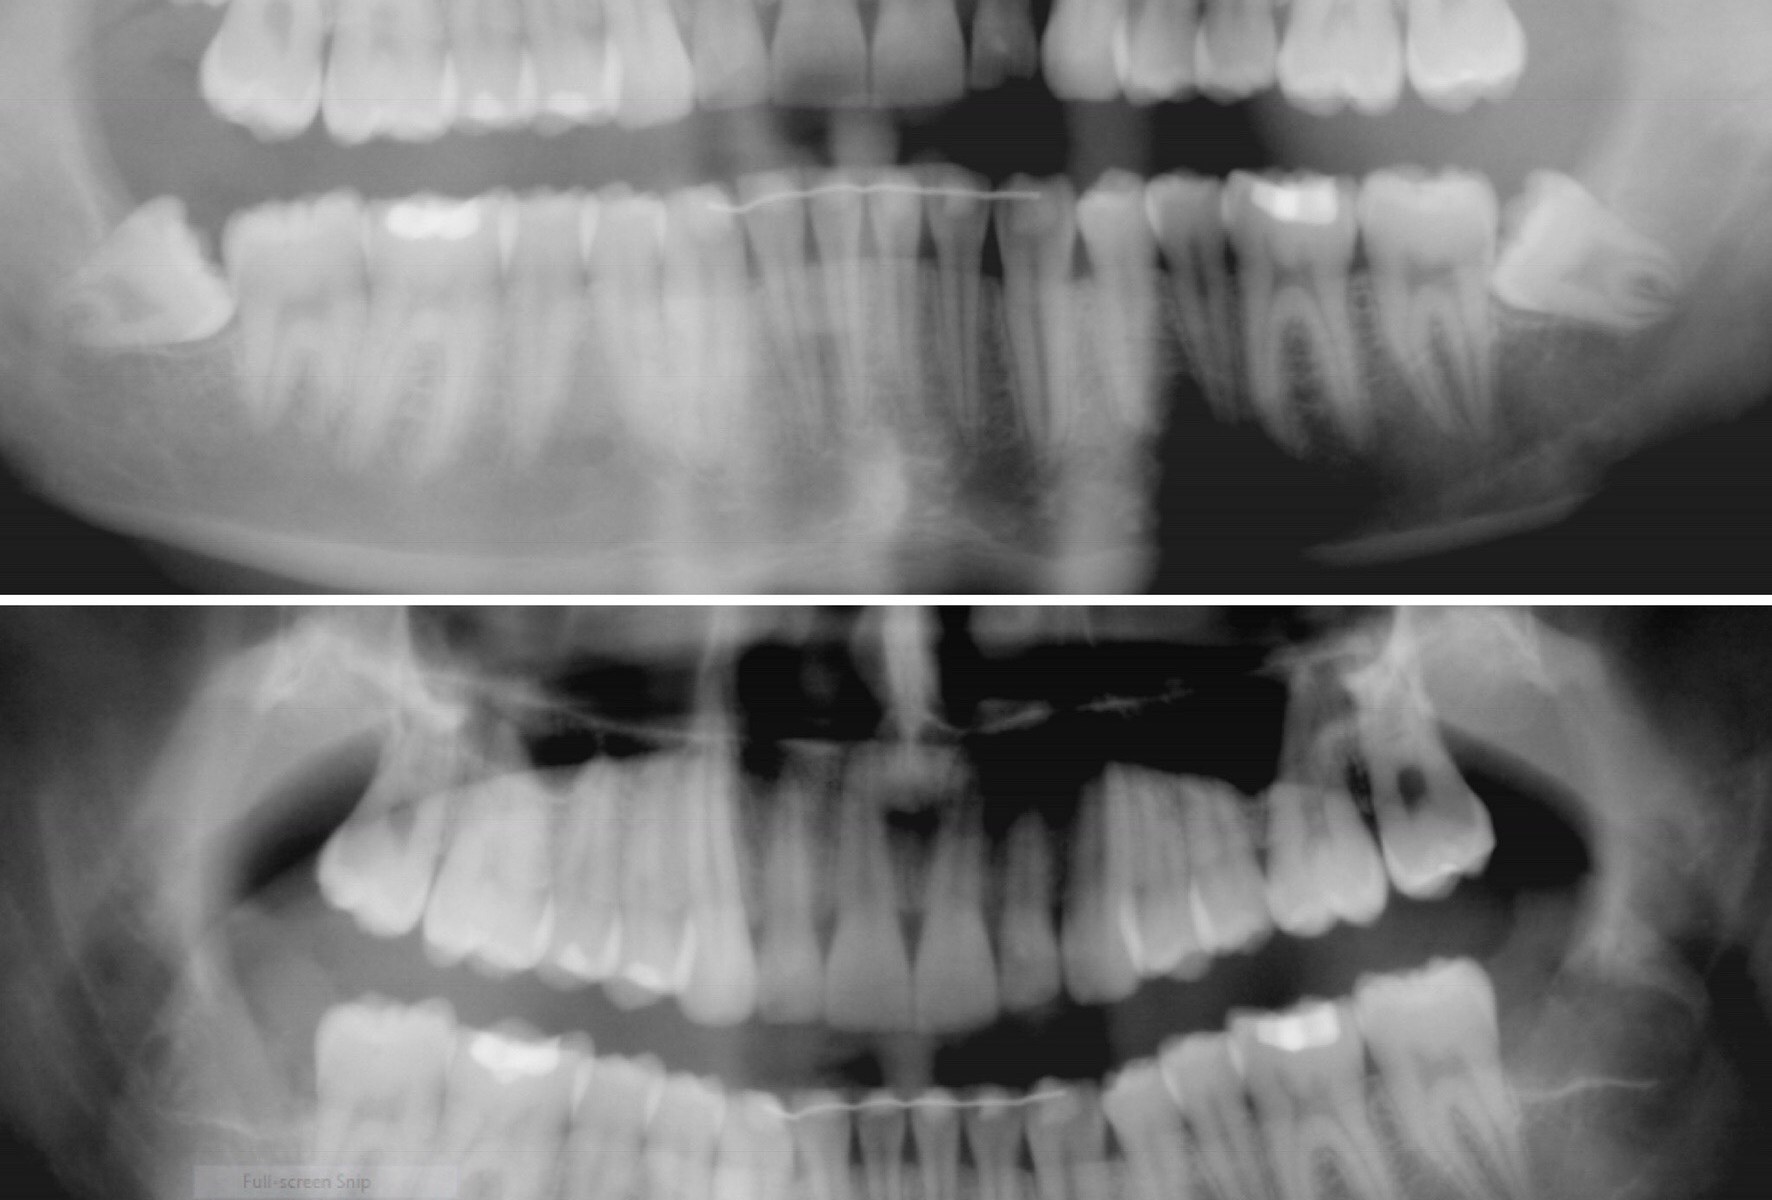

Lack of space, misalignment of teeth, and bacterial food traps are the reason we like to remove wisdom teeth. Wisdom teeth can be removed with different levels of sedation including general, IV moderate, nitrous and oral. Everyone has different needs.